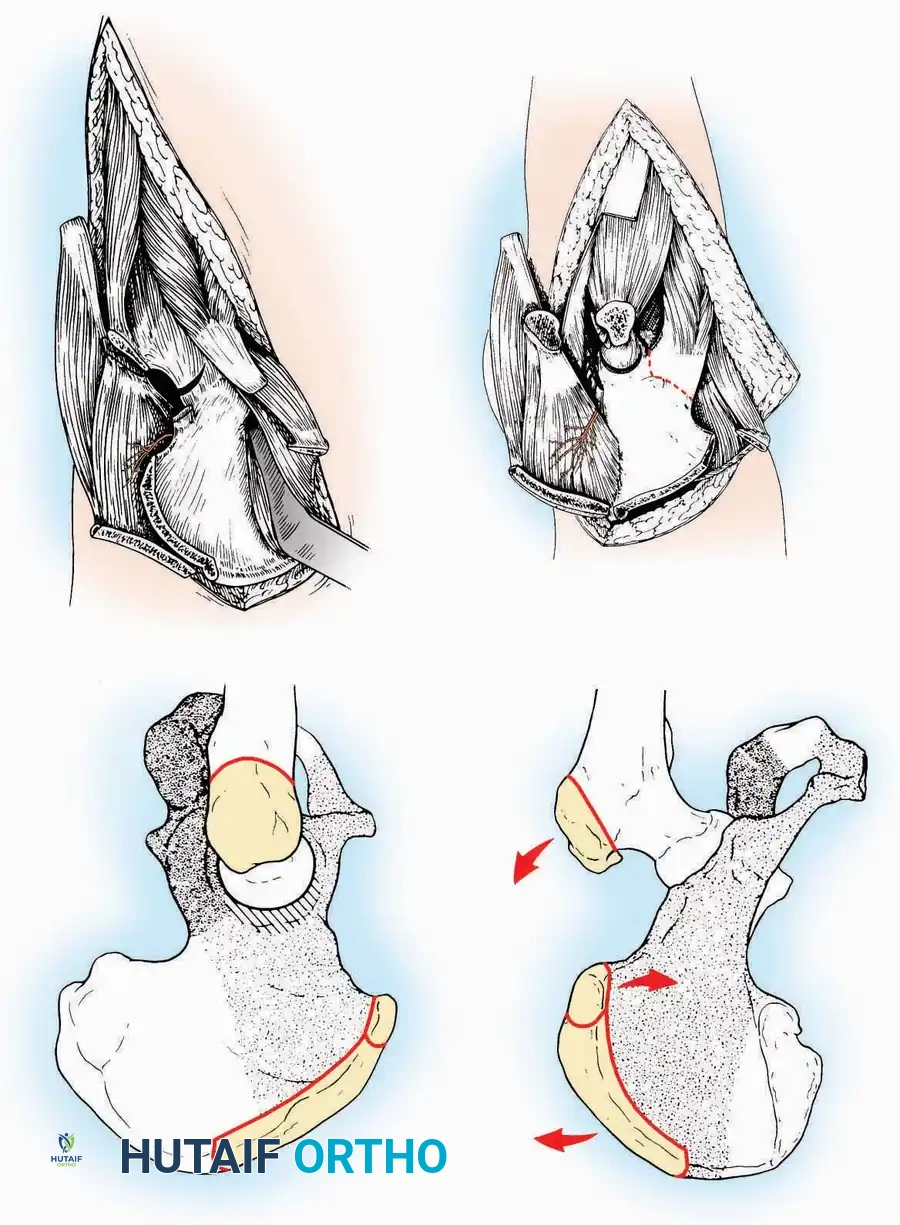

Kocher Approach (Curved L)

Indications: Complete excision of the calcaneus (calcanectomy) for malignant tumors or recalcitrant osteomyelitis.

Surgical Technique:

* Incision: Incise the skin over the medial border of the Achilles tendon, starting 7.5 cm proximal to the calcaneal tuberosity. Extend it distally to the inferoposterior aspect of the tuberosity, curve it transversely around the posterior heel, and continue distally along the lateral surface of the foot to the tuberosity of the fifth metatarsal.

* Deep Dissection: Divide the Achilles tendon directly at its insertion and carry the dissection down to the bone.

* Enucleation: To reach the superior surface, free all tissues beneath the severed Achilles tendon. The calcaneus can then be enucleated subperiosteally or extraperiosteally depending on the oncologic or infectious margins required.

Medial Approach

Indications: Fixation of sustentaculum tali fractures, medial process fractures, or excision of medial tarsal coalitions.

Positioning: Supine with the hip externally rotated and knee flexed (figure-of-four position).

Surgical Technique:

* Incision: Begin 2.5 cm anterior and 4 cm inferior to the medial malleolus. Carry it posteriorly along the medial surface of the foot toward the Achilles tendon.

* Superficial Dissection: Divide the fat and fascia to define the inferior margin of the abductor hallucis muscle.

* Deep Dissection: Mobilize the abductor hallucis muscle belly and retract it dorsally to expose the medial and inferomedial aspects of the calcaneal body.

* Plantar Exposure: Continue distally by dividing the plantar aponeurosis and the muscular attachments to the calcaneus, or strip them subperiosteally with an osteotome.

* Neurovascular Warning: Meticulously identify and protect the medial calcaneal nerve and the nerve to the abductor digiti minimi (first branch of the lateral plantar nerve), which are highly vulnerable during inferior retraction.